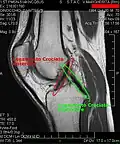

MRI

Both anterior cruciate ligament (ACL) and posterior cruciate ligaments (PCL) are hypointense on both T1 and T2 weighted images of MRI. However, some high signal striations are often seen at the distal part of the ACL, making ACL higher intensity than PCL on MRI scans.[20]

-

Knee MRI (PD TSE FS sagittal) -

Knee MRI (T1 TSE sagittal) -

Knee MRI (sagittal TSE FS)